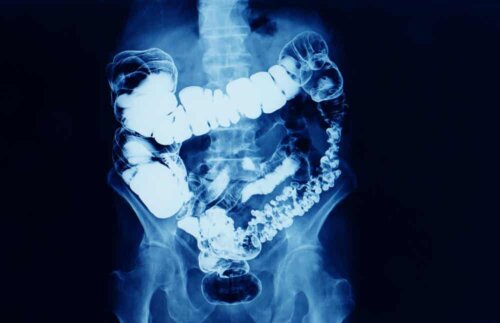

Con tumore al colon si intende la patologia oncologica che si sviluppa nell’intestino crasso e nel retto; anche nota come cancro colo-rettale.

L’intestino crasso e il retto costituiscono l’ultima parte dell’apparato digerente, dopo l’intestino tenue. È qui che si formano le feci, per poi essere espulse dal corpo portando con sé i rifiuti. Il bolo alimentare viene deidratato nell’intestino crasso e trattenuto nel retto per l’espulsione.

L’altro test è la colonscopia. Durante questo esame, effettuato sotto sedazione, viene inserito un endoscopio – un tubo flessibile con una telecamera – nel retto e nell’intestino crasso. La mucosa potenzialmente colpita può essere così osservata dal vivo, potendo prelevare campioni per la biopsia e rimuovere eventuali polipi, se presenti.